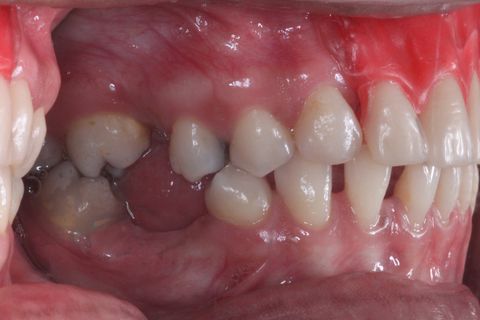

Foto de frente sem a Prótese Parcial Removível

Notar defeito ósseo.

Paciente do sexo feminino, 32 anos e 10 mêses de idade, com ausência dos incisivos centrais e laterais superiores, associado a um defeito ósseo vestibular côncavo. Realizamos planejamento reverso, ou seja, enceramento diganóstico prévio para avaliação do defeito ósseo em termos de quantidade e do posicionamento final das próteses. A paciente foi submetido a um enxerto ósseo autógeno do ramo ascendente lado direito e fixação dos blocos ósseos na área receptora, com fixação dos mesmos através de parafusos de fixação com cabeça expandida Neodent. Após 6 meses foram instalados 4 implantes Neodent.